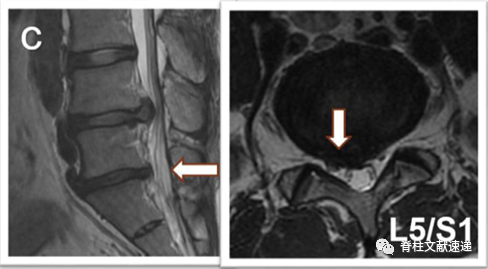

病例二:L4/5椎间盘突出症,L5/S1无症状椎间盘突出,行L4/5髓核摘除术,术后3月,L5/S1椎间盘突出,行手术治疗,如下图,c为术前,d为术后。